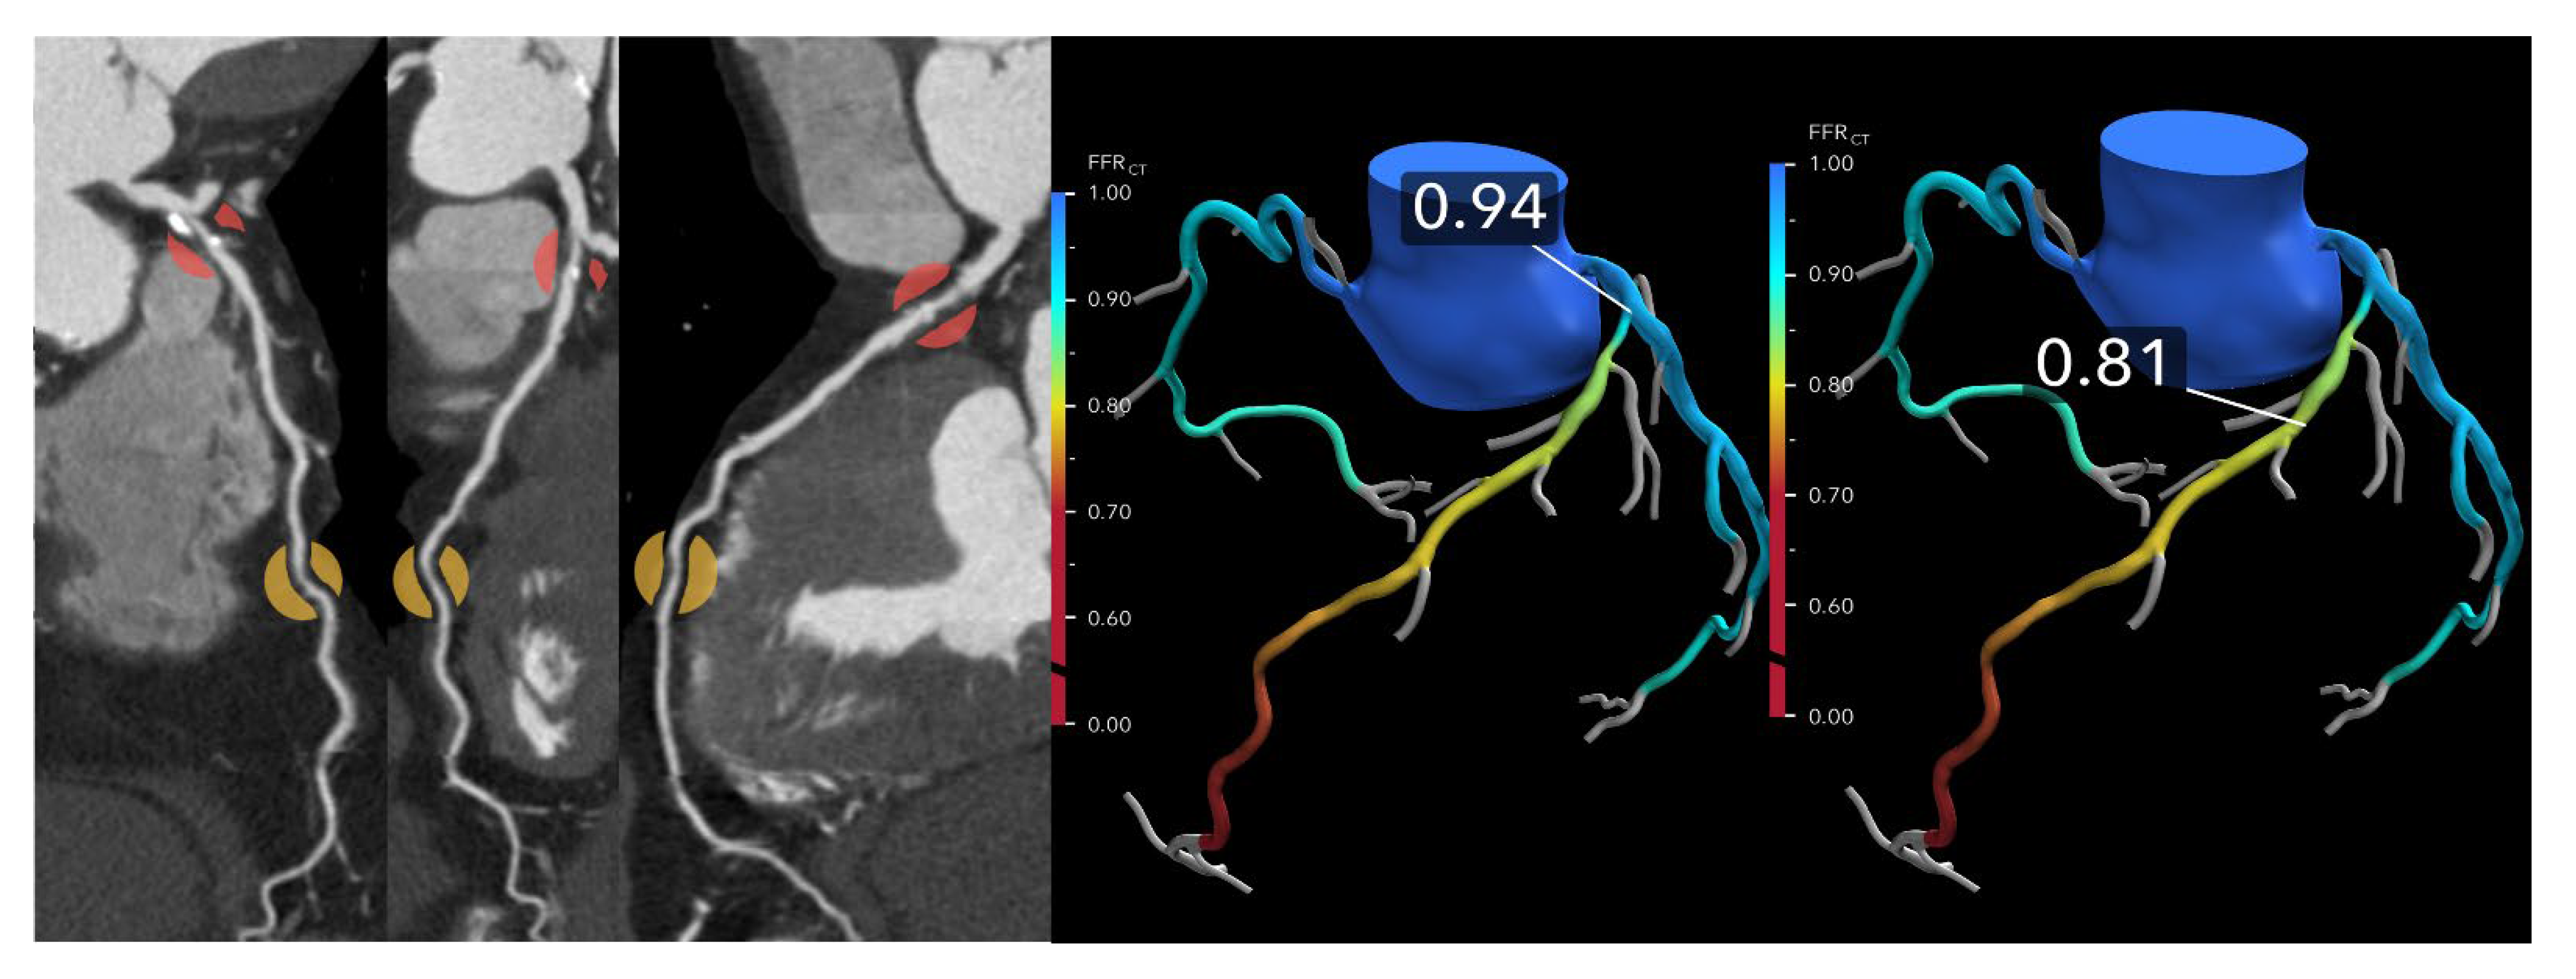

A metric to enhance physiologic interpretation of FFR-CT is the ΔFFR-CT, defined as the difference in FFR-CT values proximal and distal to a coronary lesion. In a study involving 73 vessels from 50 patients who underwent CCTA, FFR-CT, and invasive FFR, a ΔFFR-CT ≥ 0.12 strongly predicted ischemia (invasive FFR ≤ 0.80), with an odds ratio of 10.2 [23] (Figure 4). ΔFFR-CT demonstrated superior diagnostic accuracy (AUC 0.86) compared to diameter stenosis (AUC 0.66) and other FFR-CT metrics. Its integration significantly improved ischemia classification and reclassification, suggesting ΔFFR-CT may serve as a valuable adjunct, particularly in intermediate lesions or diagnostic uncertainty.

Figure 4. Lesion-specific ischemia: (Left): A curved multiplanar reformatted coronary CTA image in a 60-year-old man reveals moderate stenosis in the anterior left anterior descending (LAD) artery. (Right): The corresponding FFR-CT image shows an FFRCT value of 0.81 measured 2 cm distal to the lesion. The difference between the proximal and distal FFR-CT values across the lesion is 0.13, which exceeds the abnormal threshold of 0.12, confirming hemodynamically significant ischemia.